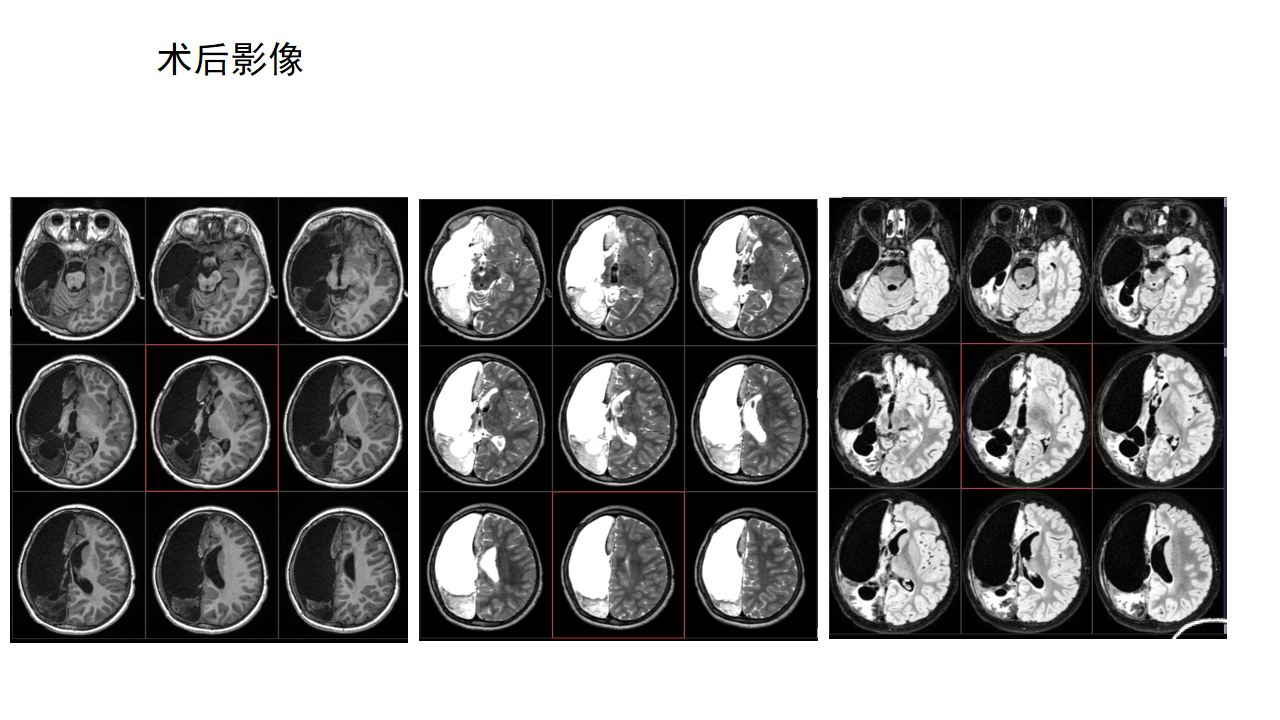

右侧功能性大脑半球切除术

杨文桢

兰州大学第二医院